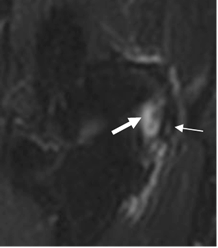

Esta condición es usualmente diagnosticada clínicamente, pero la imagen con RM es utilizada para confirmar el diagnóstico o excluir complicaciones. (3). Con esta modalidad se encuentra aumento en la SI de los tendones, por los cambios inflamatorios, difícil de diferenciar de una ruptura parcial. (3). (Fig 47).

Fig 47. Epicondilitis medial.

RM coronal en STIR. Area hiperintensa en el origen conjunto de los flexores (Flecha delgada), el cual esta rodeado por líquido. (Flecha gruesa).